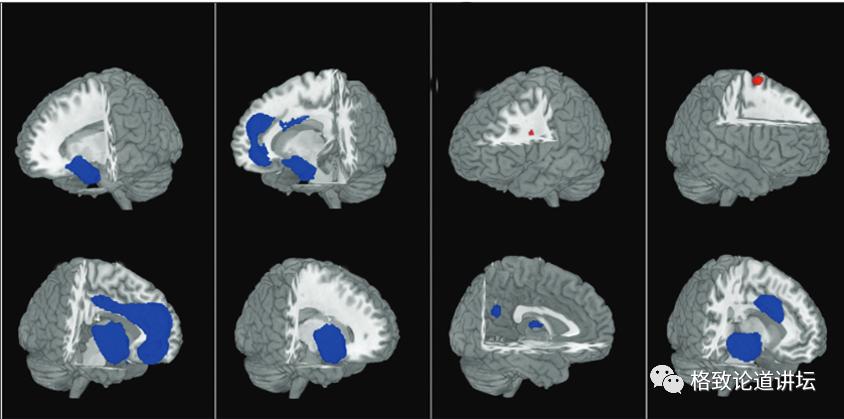

从功能核磁共振的结果可以看出,大脑的蓝色区域是有功能下降和体积缩小的,这些区域是管我们的情绪、认知、注意力、执行功能的,而红色部分跟功能调节、执行、操作有关。

从这些图可以看出,双相是由大脑病理生理改变导致的,而药物有逆转病理改变的功能,药物不仅会使神经细胞修复,而且能使神经的各个区域,尤其像额叶皮质海马这些区域的体积增大,起到修复神经的作用。